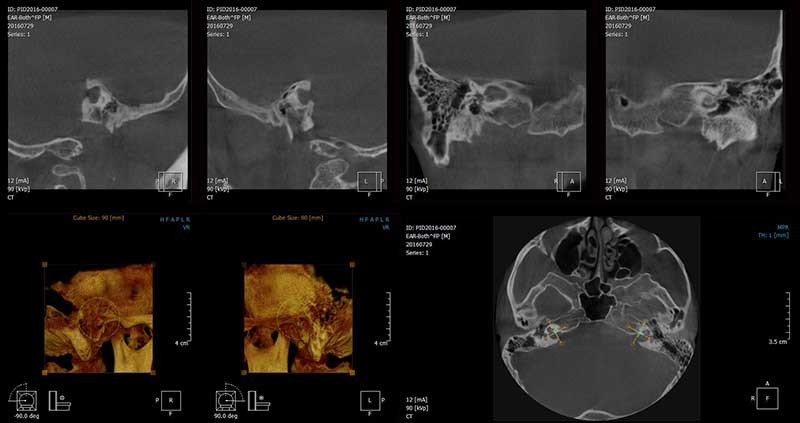

Tomografia ucha jest badaniem, podczas którego wykorzystuje się promienie rentgenowskie do uzyskania precyzyjnych, warstwowych skanów struktur ucha środkowego i wewnętrznego. Dzięki wysokiej rozdzielczości pozwala na wykrycie zmian, takich jak otoskleroza, przewlekłe stany zapalne, wady wrodzone, urazy czy nowotwory. Badanie jest bezbolesne i trwa zaledwie kilka minut. W ESDENT do jego przeprowadzania wykorzystujemy tomografy CBCT, emitujące najniższą, bezpieczną dawkę promieniowania.

Podczas RTG ucha pacjent ustawia się przed urządzeniem, a jego głowa zostaje ustabilizowana, aby uniknąć poruszeń. Tomograf wykonuje serię precyzyjnych skanów w kilku płaszczyznach, tworząc szczegółowy obraz struktur kostnych ucha. Cała procedura trwa kilkanaście sekund – podczas niej należy pozostać nieruchomym. W niektórych przypadkach stosuje się środek kontrastowy dla lepszej wizualizacji tkanek. Po zakończeniu badania specjalista analizuje obrazy i przekazuje wyniki wraz z opisem.

Oboje uszu*Parametry: 2 x12x10cm, 180µm

Ucho środkowe L lub P*Parametry: 12x10cm, 180µm

Tomografia CBCT pozwala na precyzyjną ocenę struktur kostnych i wykrycie nawet drobnych zmian, co ma kluczowe znaczenie dla planowania leczenia i minimalizacji ryzyka powikłań. Jest ona wskazana w przypadku podejrzenia otosklerozy, wad wrodzonych, przewlekłych stanów zapalnych, urazów czy zmian nowotworowych. To badanie niezbędne przed zabiegami rekonstrukcji kosteczek słuchowych, tympanoplastyką, mastoidektomią oraz implantacją ślimakową. Wykonuje się je także w diagnostyce nagłej utraty słuchu, zawrotów głowy oraz niejasnych dolegliwości bólowych.